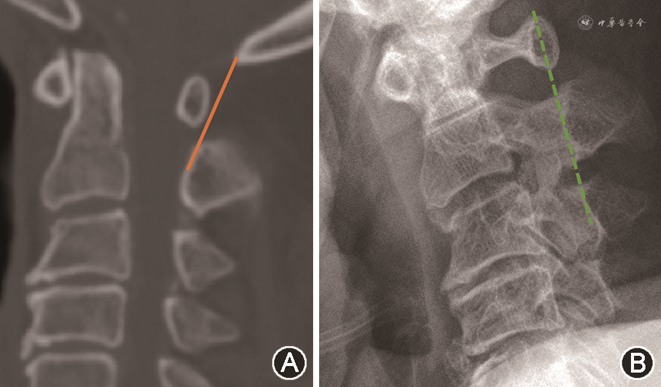

有学者提出,在颈椎侧位的X线上,通过C2以及C3的椎板的最前沿画一条直线,将寰椎后结节的前缘与此线进行比较:如果后结节的前缘触及此线或者位于此线的腹侧,则认为存在着潜在的C1水平的椎管狭窄,有着较高的敏感性及特异性[10]。因此本研究也以目前提出的C2~3椎板连线与枕枢连线两种评价方式进行了比较(图2)。

小寰椎组的16例中,有5例枕枢连线位于寰椎后弓的后1/3处,有11例枕枢连线完全位于寰椎后弓的后方。在X线上小寰椎组的病例全部符合既往的C2~3连线判定C1水平椎管狭窄的结果。小寰椎组以及对照组中,寰椎后弓与枕枢连线的位置关系的区别见图3。

本研究提出寰椎后结节垂直距离的概念,通过测量寰椎后结节前缘至枕枢连线的垂直距离,发现小寰椎组为6.79 mm,明显大于对照组的5.57 mm,说明小寰椎组的寰椎后弓明显向椎管内陷,使得脊髓后方的间隙明显小于对照组病例。本研究中,首次CT测量了寰椎后弓在枕颈区的位置关系,笔者发现枕枢连线将整体寰椎后弓分成前后两部分,小寰椎病例的这条线,不会超过寰椎后弓的后1/3部分,甚至11/16的病例的枕枢连线完全位于寰椎后弓的背侧。而正常寰椎的病例,此径线大多位于1/2处,或者是后弓的前1/3的部位,和既往的C2~3椎板连线判断C1水平椎管狭窄的方式进行的比较结果也基本吻合。当然,在对照组中也有18例枕枢连线位于寰椎后弓的后1/3甚至背侧的情况,但是经过CT上进一步测量寰椎椎管中矢状径,发现都在26 mm以上。因此,在临床上可以考虑建立一个快速的判断方法:对于寰枢椎关系正常的病例,当枕枢连线位于寰椎后结节的后1/3时,应当警惕存在小寰椎的存在,需要在CT上进一步测量寰椎椎管中矢状径的大小,明确诊断,制定手术方案。